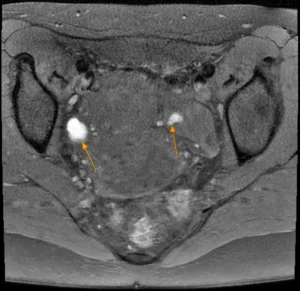

Bilaterales Endometriom | |||